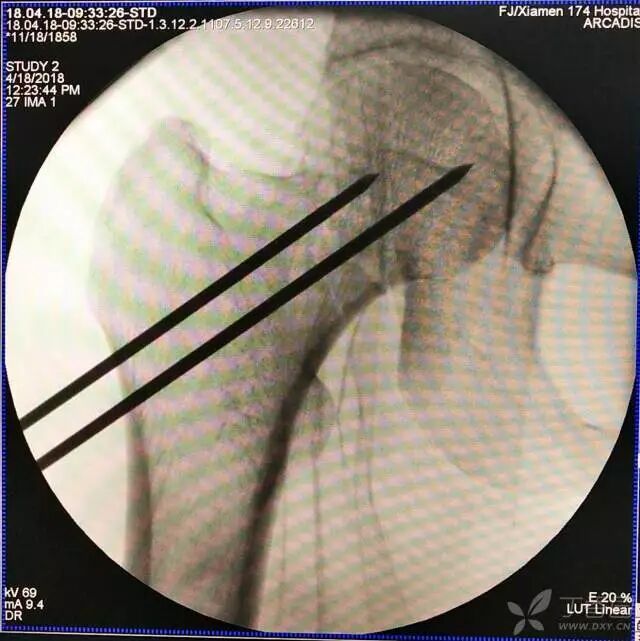

6. 然后依次打入倒品字上方的两枚导针

7. 摆 4 字位检查侧位导针的位置是否恰当